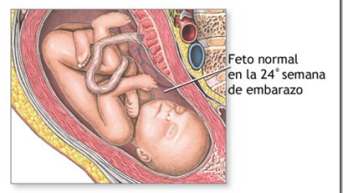

24 semanas

Já na 24ª semana, o crescimento do feto é muito rápido, chegando a pesar 500 gramas. O espaço na barriga fica cada vez mais apertado e seus movimentos cada vez mais bruscos, causando às vezes até sensações dolorosas na mãe. Seus pulmões estão cada vez mais maduros e preparados para iniciar a respiração assim que nascer. Muitas mães ficam sem saber com 24 semanas de quantos meses está, portanto falta pouco para completar o 6º mês